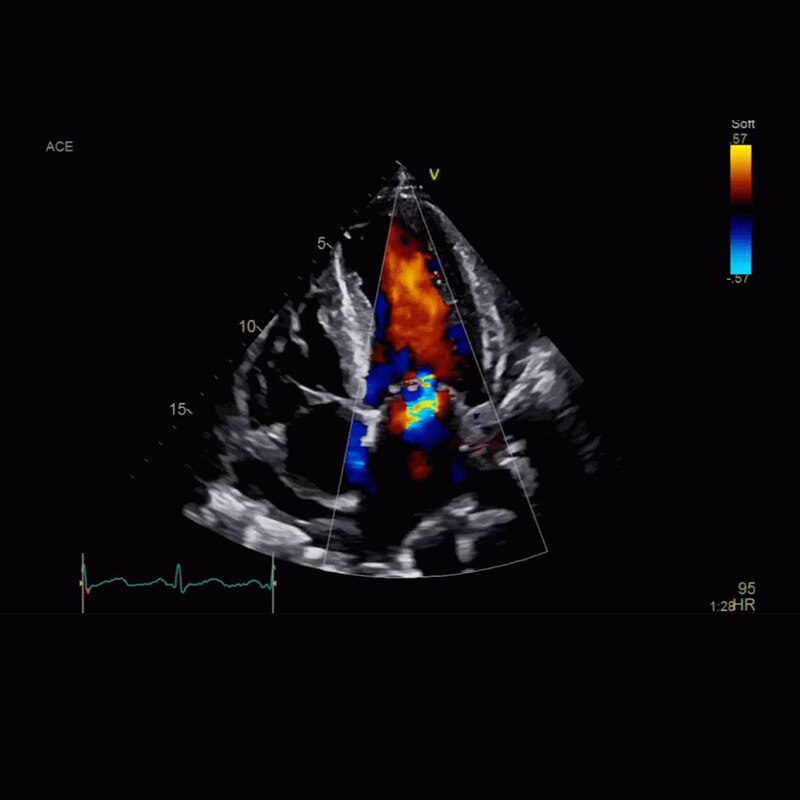

Vivid Portfolio

Cardiac Auto Doppler automatically provides Doppler measurement results for the most common parameters, with minimal user guidance.  Read More

Vivid E95

cSound™ beamforming technology for exceptional visualization quality with impressive resolution in 2D, color flow, Doppler and 4D formats.  Read More

VividTM Family Cardiac Ultrasound Automated Function Imaging (AFI)

Assess left ventricular function and cardiac performance with clarity, improving clinical confidence. Read More/span>

Vivid Family Cardiac Ultrasound

Vivid E95 with cSound performance makes 4D as easy as 2D to quantify left ventricular wall motion. Read More

Vivid E95/E90/S70N

Vivid™ Family Cardiac Ultrasound with Automated Quantification

Assess left ventricular function and cardiac performance with clarty,improving clinical confidence.Read More